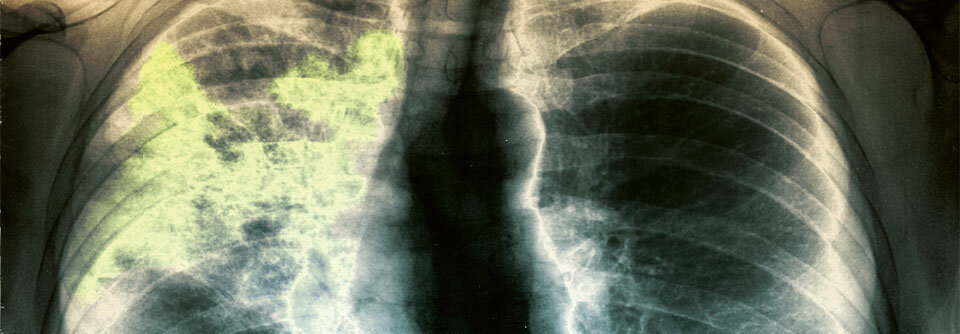

Lungenkrebs trifft auch Nichtrauchende – oft überraschend. Neue Studien zeigen: Sie haben häufiger therapierbare Genmutationen und damit bessere ...